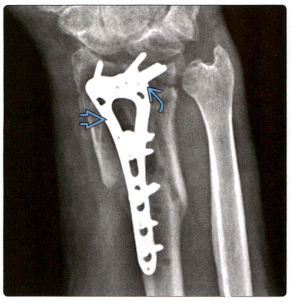

1. Косая рентгенограмма показывает: фиксированная ладонной пластинка, винты и имплантаты вышли из строя.

2. Реконструированная КТ показала: Т-образная пластина на ладонной стороне, стабилизирующая заживление перелома дистального отдела лучевой кости. Спицы Киршнера защищают перелом шиловидного отростка локтевой кости, но отмечают увеличение ладьевидно-полулунной перегородки и нижней щели лучелоктевого сустава, что указывает на повреждение связок.